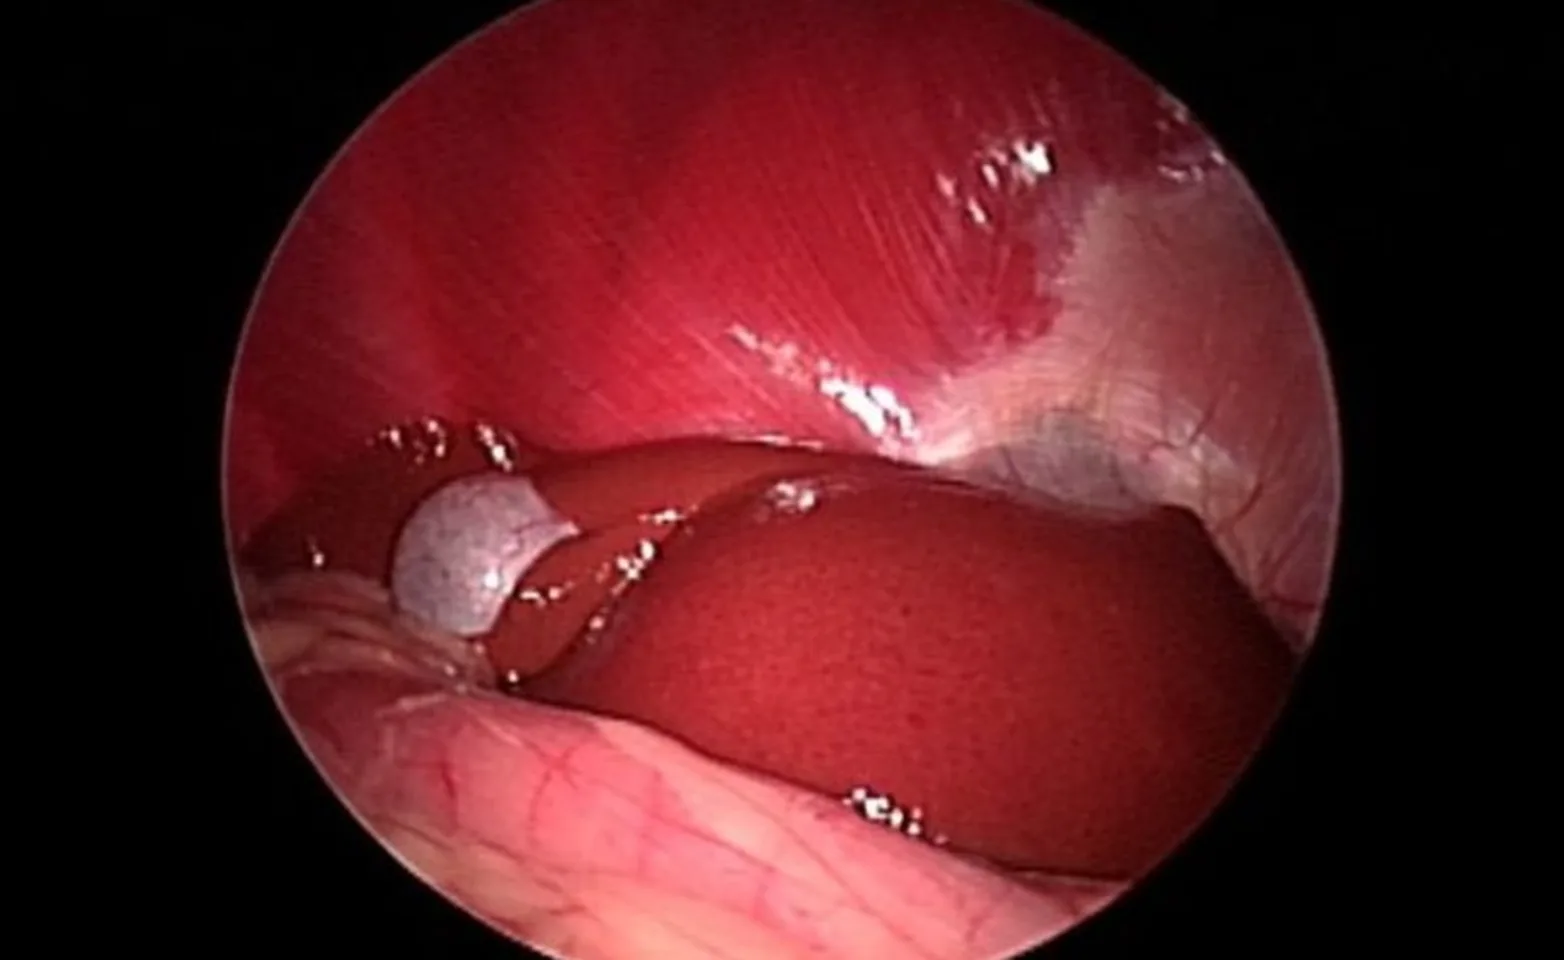

Healthy Liver